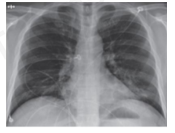

Hình ảnh ở bên là hình chụp phổi của một bệnh nhân nhiễm vi rút Covid-19. Thiết bị để chụp hình ảnh ở trên đã sử dụng tia nào sau đây?

Đáp án đúng là: B